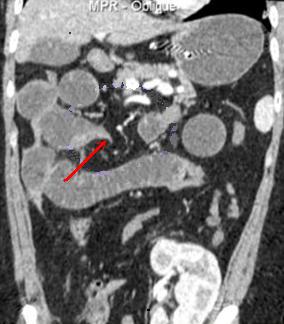

| L'occlusion par bride et

adherence represente de 50% des occlusions

intestinales . Aspect TDM particuliairement est

image de bec des oiseaux ( fleche rouge ) au niveau

de l'obtacle . Image de distension de l'intestin sus

- lesionelle et image hydro-aerique transitionnel .

L'intestin sous -lesionelle est collabe totale |